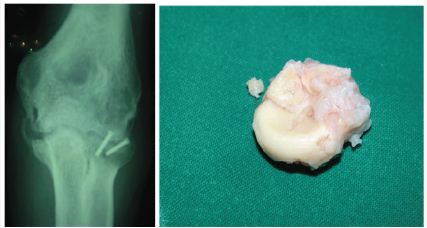

Between September 2000 and October 2012, 28 patients who fulfilled the following criteria were treated with open surgical release by one of the two senior surgeons (G.T) or (V.P.): (1) Posttraumatic stiff elbow (2) Traumatic brain injury with admission to ICU unit (3)total arc of motion of less than 100° (4) HO visible on preoperative X-ray (5) skeletally mature elbows without a history of trauma and limitation in range of motion (ROM) before injury, (6) evidence of union and stability of the joint, and (7) a normal or minimally involved ulnohumeral joint (Figure 1).

Figure 1: Typical case of elbow HO after olecranon fracture and brain injury. This patient sustained a subarachnoid hemorrhage and admitted to ICU for 20 days.

In a posterior approach a large medial and lateral full thickness fasciocutaneous flaps were created and the ulnar nerve was identified and released up to the proximal aspect of the flexor carpi ulnaris (FCU) muscle and protected (Figure 4). After dissection of the triceps muscle from the posterior humerus, a complete excision of the posterior capsule was performed as well as excision of heterotopic bone from the posterior aspect of the joint, especially around the olecranon and the olecranon fossa. If necessary, the posterior band of the MCL was released, until gaining flexion up to 130 degrees or more. When forearm motion was limited the Kocher interval was developed and an anterior capsulectomy was performed in combination with excision of heterotopic bone whenever it was present. In five cases a radial head excision was undertaken due to enormous enlargement from chondral metaplasia, after radial head fracture (Figure 5). In six cases a medial approach through the flexor-pronator mass was developed, one primarily and the rest as a part of another approach, in order to completely excise the anterior capsule and achieve full extension of the joint.

Figure 5: Elbow HO after brain injury and Radial head fracture. a)HO in the lateral and medial side. b)Radial head chondral metaplasia